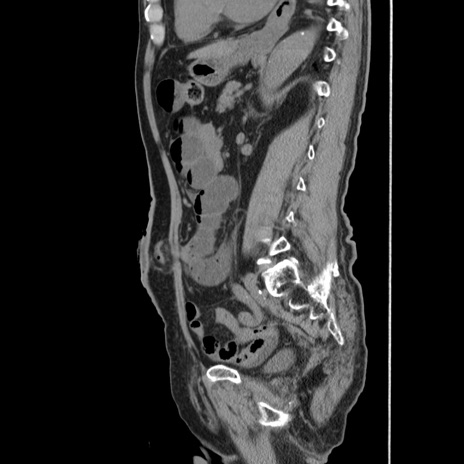

症例24(矢状断像)

【症例】80歳代男性

【主訴】左側腹部痛、嘔吐

【現病歴】本日早朝より左腹部に痛みあり。昼頃嘔吐認めたため、救急要請。

【既往歴】直腸癌(Mile手術)、胆摘

【身体所見】意識清明、BT 35.9℃、BP 221/93mmHg、SpO2 97%(RA) 、腹部:左ストーマ周囲に限局性の腹部膨隆あり。 膨隆部自発痛・圧痛あり・軟。

【データ】WBC 7700、CRP 0.09